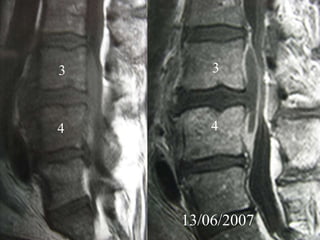

4th case

D.N.

M 61– Cardiologist

Symptoms

 Severe Neurologic deficit

 Intensive Thoracic-lumbar Pain

 High fever

Laboratory

 Neutroph. ↑

 SR 60

PMH

 Heavy smoker

 Diabetes melitus

 Recent Elbow Furuncle (untreated)

Elbow furuncle

13/06/2007

3

4

Anterior

PUS evacuation

Bilaterally

Laminectomies

Post posterior PUS

evacuation

Follow up

Pus culture

(staphylococous aureous)

Antibiotics

 i-v for 2 mts

 orally for 7 mts

Complete neurologic recovery